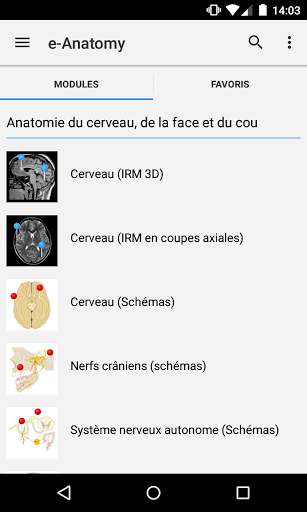

New : You can now filter the modules by region or by content type so you can find the module you are looking for much faster.